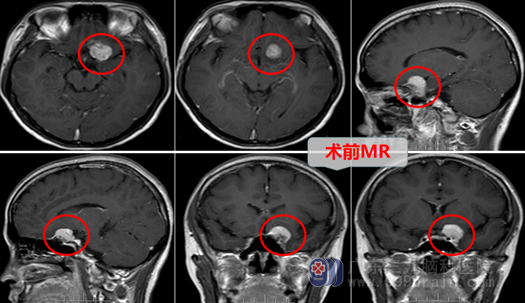

曾姐感觉头颈部疼痛不适,刚开始,并没放在心上,想着顶多也就是肩周炎或者是颈椎病,没想过:“自己那么年轻,还会有什么脑病?”,心想休息休息就好了,但是这次却出乎意料,都几周了头痛还不见改善,曾姐就不得不去了当地医院就诊,医生为她做了头部MR检查,真是:不做不知道,一做吓一跳,MR示“左侧蝶骨嵴脑膜瘤”,这下曾姐真被吓到了,才30多岁,医生说要尽快手术,要开颅,曾姐和家人害怕的不得了,主要是担心术后恢复不好,她还这么年轻,怕成为家里的负担,曾姐的家人经多方打听,得知广东三九脑科医院神经外十科欧阳辉教授团队是国内权威的脑科团队,于是就慕名到广东三九脑科医院就诊,主管医生邓心情拟“左侧蝶骨嵴脑膜瘤”收入我科。

入院后,邓心情医生尽快给曾姐完善了各项术前检查和准备工作后,欧阳辉教授带领团队进行了详细的讨论及手术安排,蝶骨嵴内侧型脑膜瘤手术难度比较大,容易损伤颈内动脉、大脑中动脉、视神经等重要结构,要求有娴熟的显微神经外科技术。

2022年6月28日欧阳辉教授团队为曾姐进行了“左侧内侧型蝶骨嵴脑膜瘤切除术”,术中:医生在高清智能显微镜的帮助下,认真仔细操作,雕刻式分离、切除肿瘤,妥善保护神经血管,结果:完全切除了肿瘤,且并未损伤正常组织结构。术后:曾姐神志清醒,回答正确,四肢活动都是很好的,恢复几天后,再也没有出现像手术前那样的头颈痛等不舒服的症状。